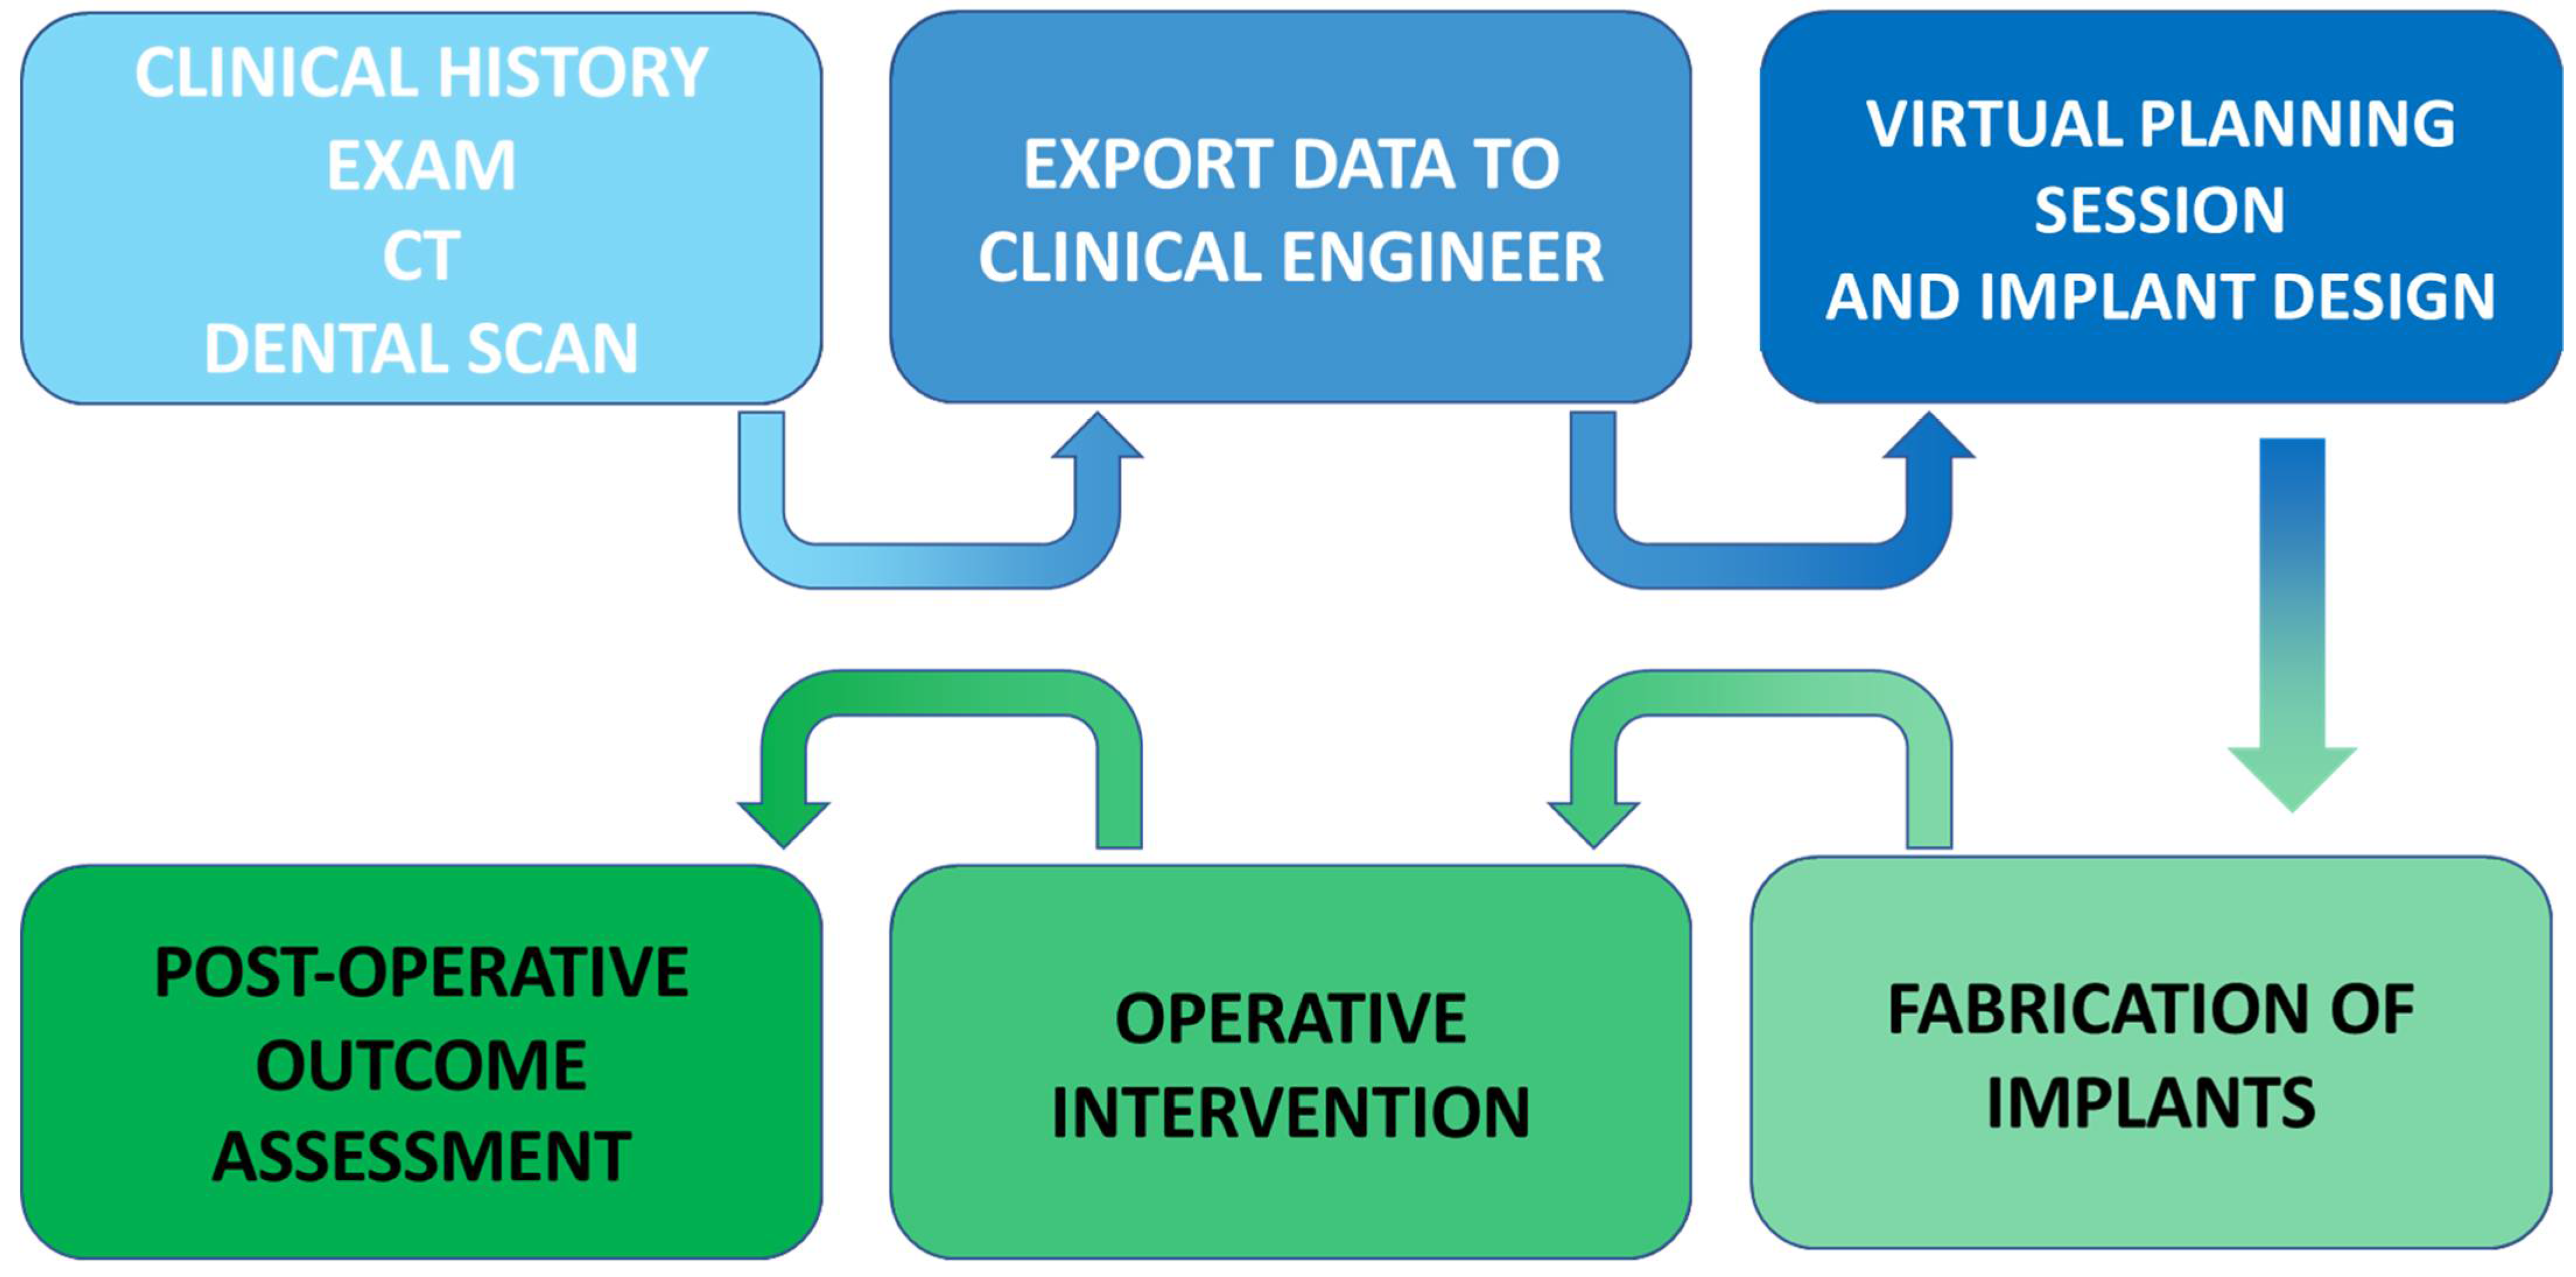

5. In-House Computer-Assisted Surgical Planning